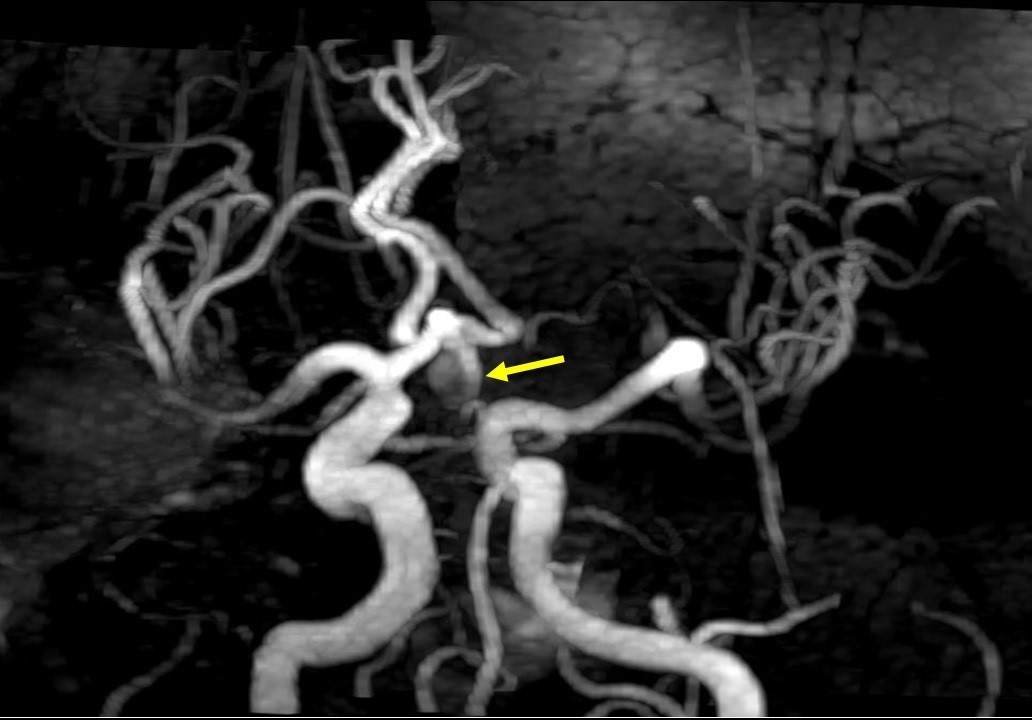

Imagen 1: Visión oblicua posterior izquierda de reconstrucción MIP de angioRM con técnica 3D TOF que demuestra la existencia de un aneurisma sacular de gran tamaño y morfología ovalada dependiente de la arteria comunicante anterior (flecha amarilla). El aneurisma surge de la bifurcación del segmento A1 de la arteria cerebral anterior izquierda en ambos segmentos A2 debido a aplasia de segmento A1 derecho.

Se obtienen series angiográficas en proyecciones anteroposterior y lateral de cráneo y adquisición rotacional con reconstrucción 3D que confirman la presencia de un aneurisma sacular de arteria comunicante anterior, de aproximadamente 3mm de cuello por 6mm de diámetro máximo y 8 mm de fondo, en dirección anterocaudal, coexistiendo aplasia del segmento A1 de la arteria cerebral anterior (ACA) derecha por lo que el flujo de ambas AACCAA depende del eje carotídeo izquierdo (imagen 2).